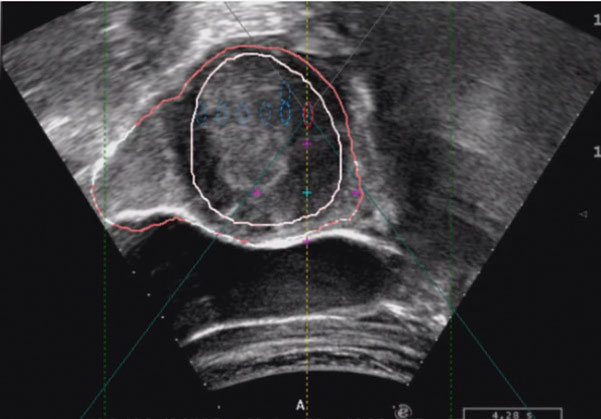

在影像技术中,图像融合技术(image fusion,IF)是将多模态图像相互融合互补。通过多种成像模式以提供更全面的信息。这里所说的图像融合技术,主要是指解决超声监控图像出现伪影干扰、肿瘤边界显示不清楚、定位时间延长、治疗时间延长及治疗不彻底等问题。将患者治疗前MRI或CT的序列图像通过计算机与监控超声图像进行重建,即可获得多模态融合的图像。当监控超声图像受到干扰时,在干扰区域可以提取相应的MRI或CT图像信息进行充填,以弥补超声监控图像的不足。

不过IF还在不断完善之中,目前要解决的关键问题是确定两种融合图像的空间位置,因为空间位置不匹配,融合的图像并不能保证在同一位置,即所谓错位,一旦发生错位就存在潜在风险。总之,图像融合技术是超声引导监控HIFU治疗的发展方向之一,现已逐渐用于临床,其造影效果见图4-1。

图4-1 实时超声影像(包含特征轮廓)